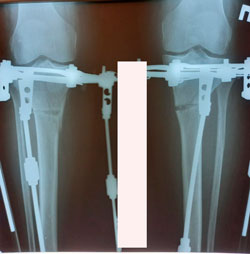

на фиксации